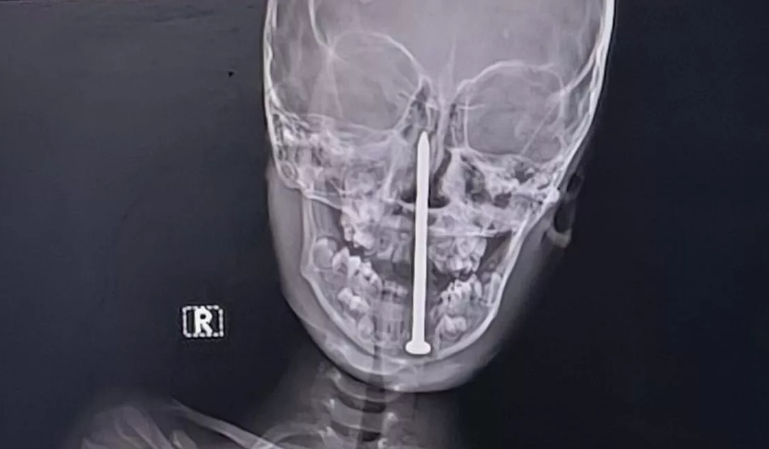

▲男童玩耍時不慎跌倒,整根長達8公分的鐵釘插入頭部。(示意圖,非當事畫面/CFP)

印度北方邦(Uttar Pradesh)一名7歲男童日前在玩耍時不慎跌倒,整根長達8公分的鐵釘插入頭部,甚至刺進腦內,家屬嚇得連夜送醫,歷經高風險的10小時手術後,男童奇蹟生還。

金喬治醫科大學(King George's Medical University)創傷外科主任蒂瓦里(Sandip Tiwari)表示,經MRI與CT掃描後發現,鐵釘尖端已深入腦部,距離主要血管只有一點點的距離,情況十分危急,「能避開血管實在是奇蹟。」

醫療團隊最終決定進行一場高難度手術,結合顯微手術與神經導航技術,小心翼翼地將這根長達8公分的鐵釘取出。整場手術耗時10小時,過程驚險萬分,但在團隊精準操作下成功完成。